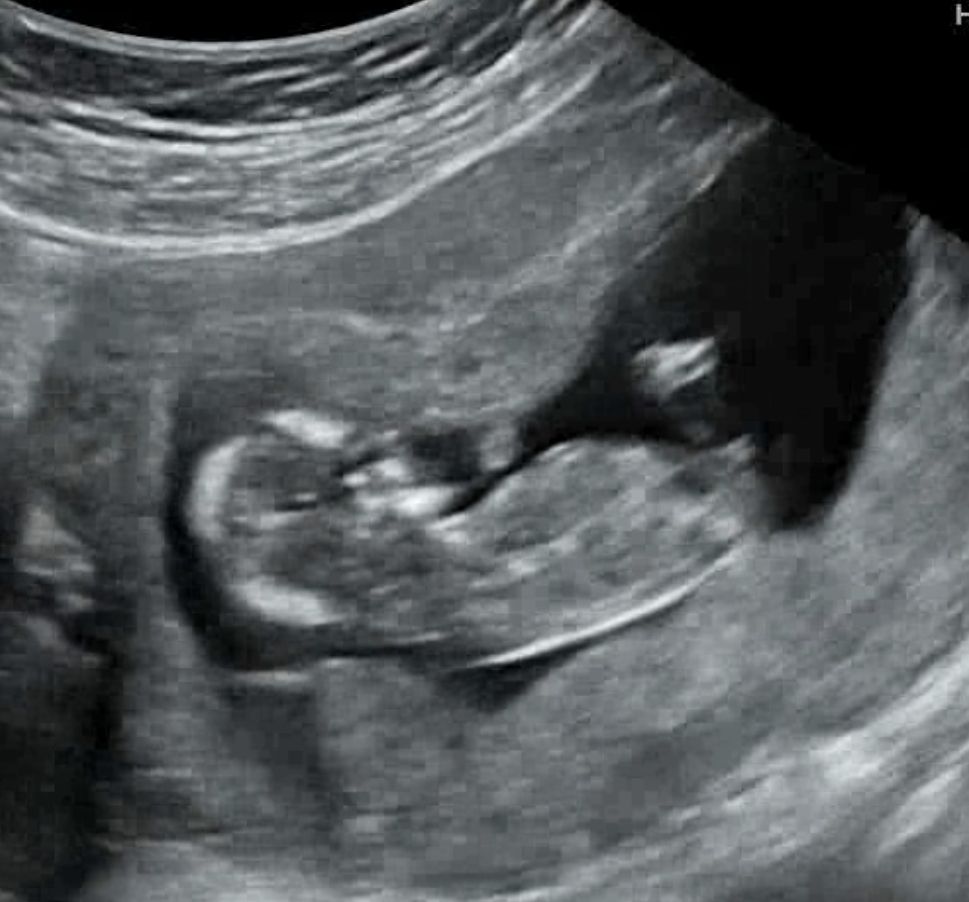

12주. 각도법 봐주시면 복 받으십니다!!

안녕하세요. 금일 12주 1일차 초음파 검사 보고왔는데 그 유명한 각도법에 대입하려해도 애기가 일직선으로 누워있는게 아니니 어렵네요~ 이 위치에 '그게' 맞는건지...ㅜㅜ 그리고 각도상 남아일지 여아일지!! (애기 척추라인이랑 연결해서 봐주세요🙌) 가볍게 봐주시고 투표 부탁드립니다!